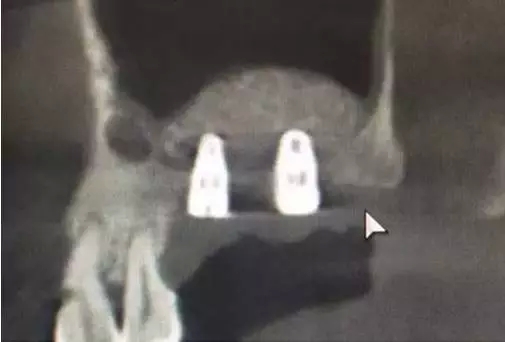

植入兩顆植體。

術(shù)后6,7牙位CT片,顯示充足的植骨量。

整個(gè)手術(shù)時(shí)間僅20分鐘,充分體現(xiàn)了:安全、方便、快捷的原則。